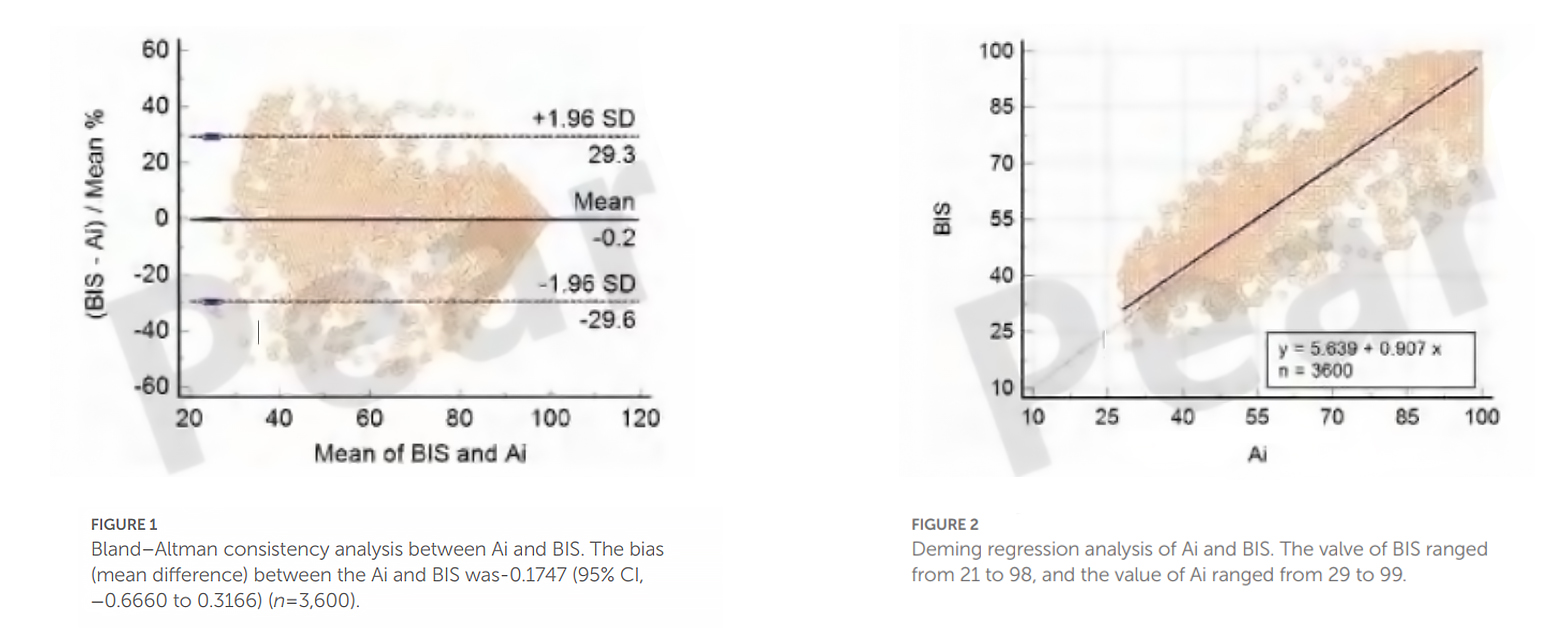

The following are a large number of statistical indicators of AI and BIS obtained under clinical verification, and the results show that the Ai index and the BIS index have significant consistency.